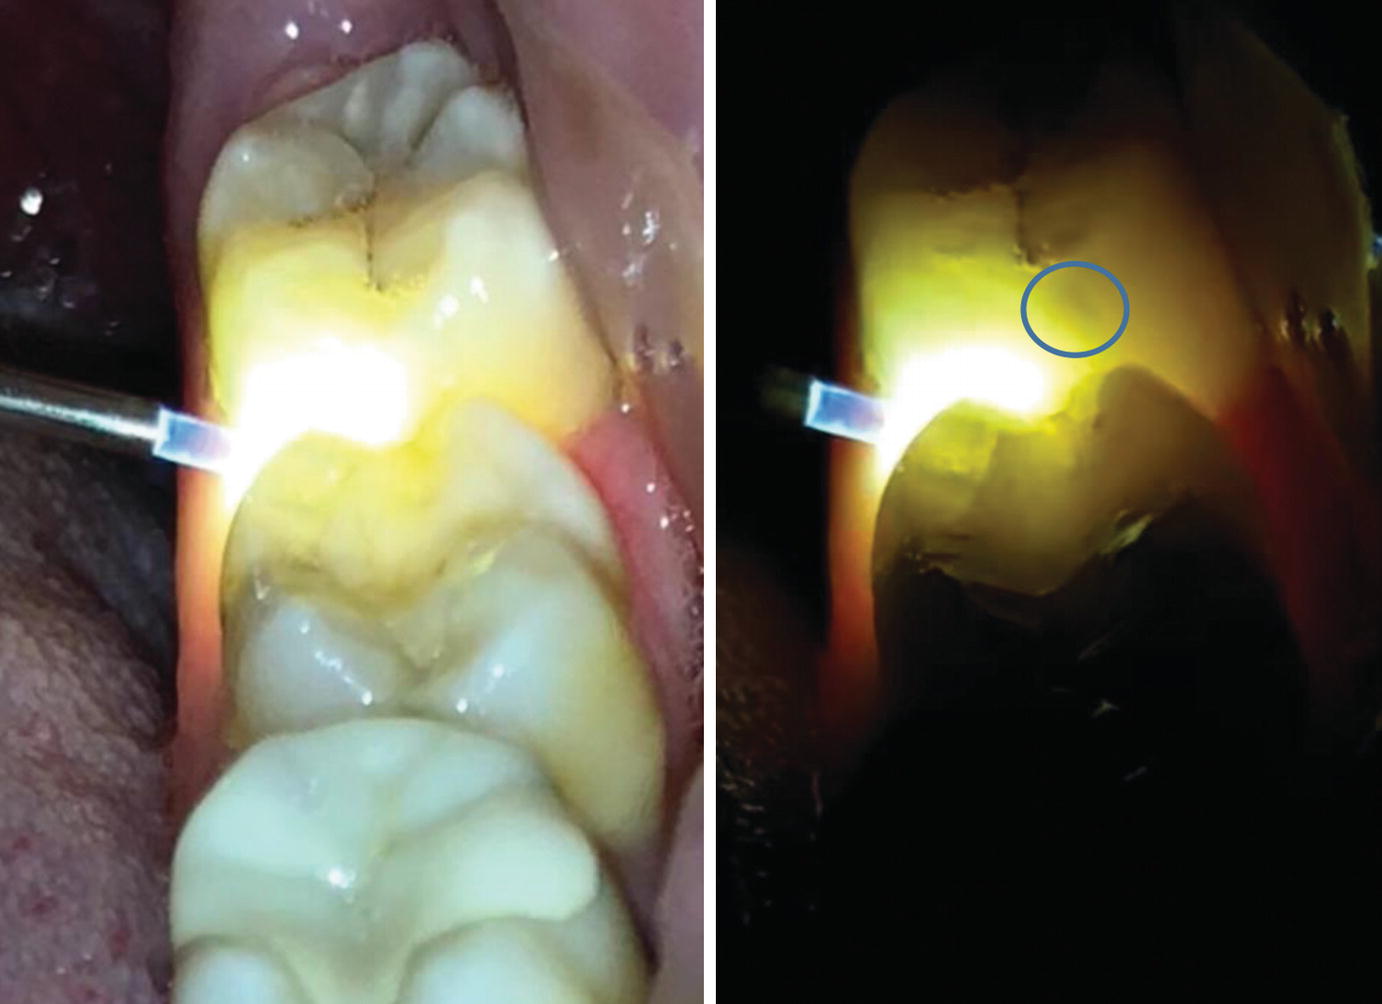

Fiber Optic Light In Dentistry . In this study, we focus on transillumination methods: Fibre optic transilumination (foti) in dentistry, transillumination. In dentistry, foti has been primarily associated with caries diagnosis and has been corroborated through research studies to be a valid indicator. The importance of probe placement in the foti technique and the effect. Fiber optic transillumination is an operator sensitive technique.

The importance of probe placement in the foti technique and the effect. Fibre optic transilumination (foti) in dentistry, transillumination. In this study, we focus on transillumination methods: Fiber optic transillumination is an operator sensitive technique. In dentistry, foti has been primarily associated with caries diagnosis and has been corroborated through research studies to be a valid indicator.

Fiber Optic Light In Dentistry The importance of probe placement in the foti technique and the effect. In dentistry, foti has been primarily associated with caries diagnosis and has been corroborated through research studies to be a valid indicator. In this study, we focus on transillumination methods: Fiber optic transillumination is an operator sensitive technique. The importance of probe placement in the foti technique and the effect. Fibre optic transilumination (foti) in dentistry, transillumination.